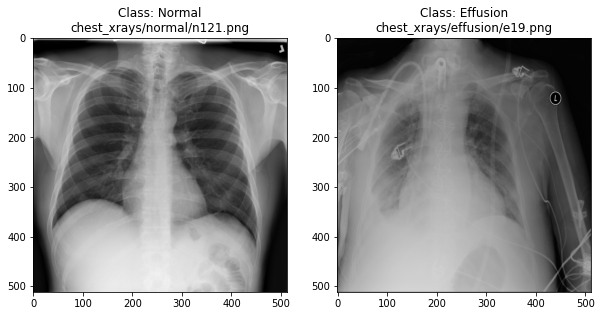

In the previous section, we set up a dataset comprising 700 chest X-rays. Half of the X-rays are labelled “normal” and half are labelled as “pleural effusion”. Let’s take a look at some of the images.

Here we see that the image has 3 dimensions. The first dimension is height (512 pixels) and the second is width (also 512 pixels). The presence of a third dimension indicates that we are looking at a color image (“RGB”, or Red, Green, Blue).

For simplicity, we’ll instead load the images in greyscale. A greyscale image has two dimensions: height and width. Greyscale images have only one channel. Most greyscale images are 8 bits per channel or 16 bits per channel. For a greyscale image with 8 bits per channel, each value in the matrix represents a tone between black (0) and white (255).